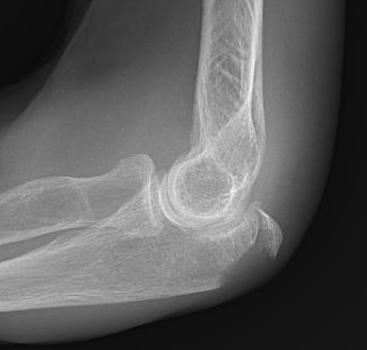

Xray

Olecranon avulsion